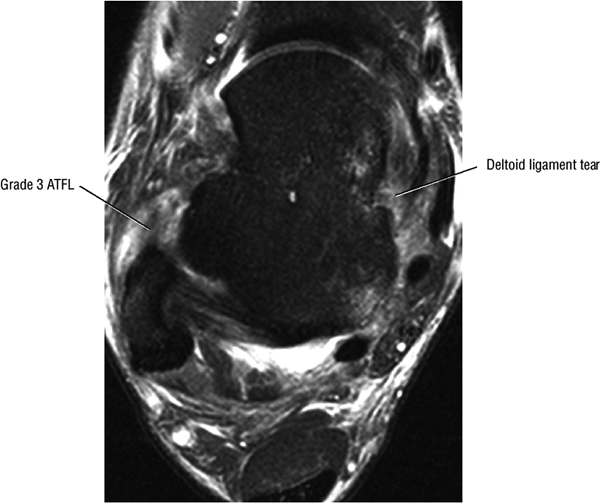

|

![]() |